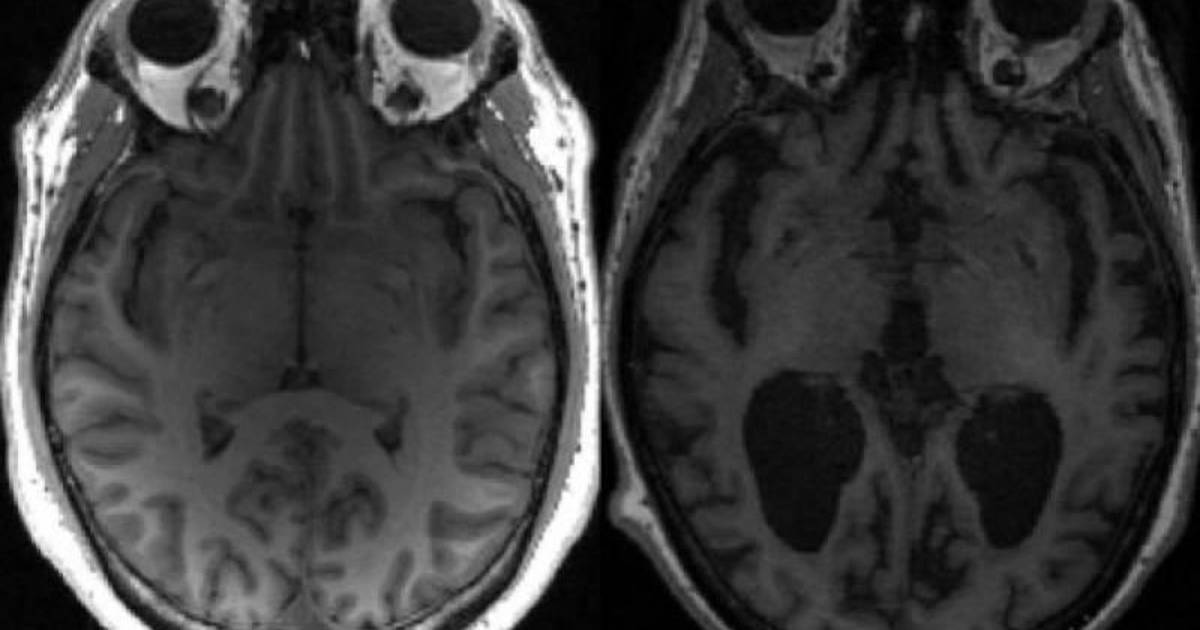

En la enfermedad de Alzheimer, dos proteínas clave -la tau y otra llamada beta-amiloide- se acumulan gradualmente de forma anormal en el cerebro, provocando la muerte de las células cerebrales y el encogimiento del cerebro.

Esto provoca la pérdida de memoria y una creciente incapacidad para realizar las tareas cotidianas.